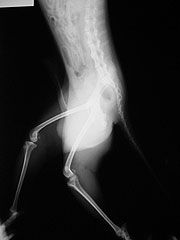

受傷時,肩關節內維持穩定的重要構造(肩盂唇韌帶),因關節脫位而從間盂的邊緣撕裂,並且和骨頭剝離。之後雖然關節復位,但受傷的部位沒有癒合,形成一永久性的缺口,而無法維持肩關節的穩定度。90%以上的肩關節脫位都是由前方脫出,所以,肩盂唇韌帶剝離處亦位於肩盂的前下方,也就是如此;再脫位都發生在肩上舉外展及外轉的動作。另外脫位次數多了,前方的關節囊亦被”撐〃的變成愈來愈鬆弛,也使得脫位愈易發生。脫位一次,關節就受傷一次,不但會造成關節軟骨磨損或是剝離掉落,甚至也會造成上盂唇韌帶的撕裂。大多數的病人對於肩關節”進進出出〃的不穩定不以為意,認為只要多加注意某些不良姿勢或避免某些活動,其就可以減少脫位發生的機會;有些人也認為許久才脫出一次影響不大;更有人認為自己愈來愈會自行復位,是否病情減輕了?近來愈來愈多的研究報告及我們自己的經驗顯示,常時間的肩關節不穩定,累積了多次的脫位或半脫位,這都會造成關節軟骨的磨損,而有很大的機會得到肩關節炎